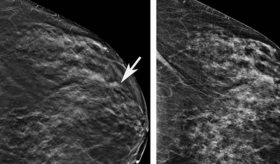

El uso de productos capilares para teñir y modificar la textura del cabello en la adolescencia aumenta el riesgo de padecer cáncer de mama.